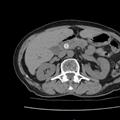

Ống tiêu hóa là một cơ quan rất khó chẩn đoán bệnh lý. Các phương pháp hiện đại như siêu âm, chụp cắt lớp điện toán (CT) hay cộng hưởng từ (MRI) dù rất đắt tiền nhưng vẫn không có giá trị trong chẩn đoán chính xác bệnh lý ống tiêu hóa. Qua nội soi giúp: